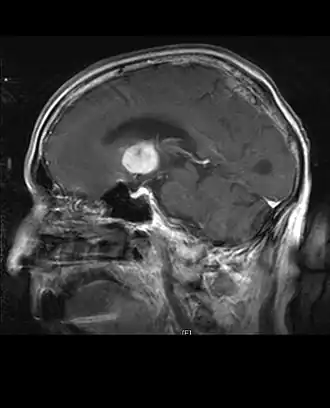

Beelddiagnose

Computertomografie (CT) en magnetische resonantiebeeldvorming (MRI) kunnen neoplasie in de hersenen effectief detecteren. MRI is gevoeliger dan CT voor het identificeren van laesies, maar heeft contra-indicaties voor patiënten met pacemakers, incompatibele prothesen, metalen clips en andere. CT blijft de voorkeursmethode om calcificaties in laesies of boterosie van het kalotje of de basis te detecteren. Het gebruik van contrastmiddelen, die gejodeerd zijn in het geval van CT en paramagnetisch (gadolinium) in het geval van MRI, maakt het verkrijgen van informatie over de vascularisatie en integriteit van de bloed-hersenbarrière mogelijk, een betere definitie van de tumorachtige tumor vergeleken tot het omringende oedeem en het genereren van hypothesen over de mate van maligniteit. Het radiologisch onderzoek maakt ook een beoordeling mogelijk van de mechanische effecten en de daaruit voortvloeiende veranderingen in hersenstructuren als gevolg van de tumor, zoals hydrocefalus en hernia's, waarvan de effecten fataal kunnen zijn. Ten slotte kan deze diagnostiek, ter voorbereiding op een operatie, worden gebruikt om de locatie van de laesie of de infiltratie van de tumor in vitale delen van de hersenen te bepalen. Voor dit doel is MRI efficiënter dan CT omdat het driedimensionale beelden kan opleveren. Diagnostische radiologische beeldvormingshulpmiddelen benadrukken de verandering in neoplastisch weefsel in vergelijking met normaal hersenparenchym (door veranderingen in elektronisch afgebeelde weefseldichtheid op CT en signaalintensiteit op MRI). Zoals de meeste pathologische weefsels zijn tumoren ook herkenbaar aan een verhoogde ophoping van intracellulair water. In het computertomogram lijken ze hypodens, dwz met een lagere dichtheid dan het hersenparenchym, in het kernmagnetische resonantietomogram met spin-roosterrelaxatie hypointenseen in spin-spin ontspanning evenals proton weging (PD) hyperintens.

Het gezonde deel van de hersenen mag geen specifieke luminescentie vertonen op een radiologisch beeld. Het spreekt dan ook voor zich dat er aandacht wordt besteed aan grotere contrastsignaalbereiken.

In tumorweefsel is in het algemeen het grotere aandeel van contrastversterking te wijten aan de specifieke bloed-tumorbarrière die de doorgang van jodium (CT) en gadolinium (MRI) naar de intratumorale extravasculaire interstitiële ruimte mogelijk maakt. Dit verhoogt het signaal (dichtheid of intensiteit) van de tumor. Er moet echter voor worden gezorgd dat contrastversterking geen definitief onderscheid maakt tussen neoplasie en oedeem rondom de wond. In feite is de anatomische-pathologische bevinding in kwaadaardig infiltrerend glioomtumorweefsel, zoals in glioblastoom en anaplastisch astrocytoom, ook te zien buiten het vasogeen oedeem veroorzaakt door de vernietiging van de bloed-hersenbarrière door de tumor. De laatste klinische aandoening is slecht detecteerbaar door diagnostische beeldvorming.

Computertomografie van de hersenen toont typisch een weefselmassa die door beide contrasten kan worden versterkt. Op CT lijken laaggradige gliomen gewoonlijk isodense aan het normale parenchym en vertonen daarom mogelijk geen contrastversterking. Evenzo zijn laesies in de achterste schedelgroeve moeilijk te identificeren op CT. Bijgevolg zijn de resultaten van een dergelijke tomografie alleen niet altijd voldoende voor diagnostische doeleinden. In twijfelgevallen is het gebruik van de meer gevoelige magnetische resonantiebeeldvorming essentieel.

Aan -MRI toont een intracraniële tumor als een massieve laesie die na gebruik van het contrastmiddel meer luminescent kan worden. Er is echter altijd een signaalafwijking in -Magnetic resonance imaging, die de aanwezigheid van neoplasie of vasogeen oedeem aangeeft. Gewoonlijk is verhoogde luminescentie (contrastversterking) indicatief voor een tumor met een hogere graad van maligniteit. Kenmerkend voor glioblastoom is een contrastring, waarbij het lichtgevende deel overeenkomt met het vitale deel van de kwaadaardige tumor en het donkerdere -hypointens gebied dat overeenkomt met weefselnecrose.